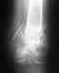

Re: Перелом голени со смещением отломков

Благодарю Вас что откликнулись! Такие таблетки, мне врач выписал. Мой врач говорит, что снимки нормальные, что мне делать?